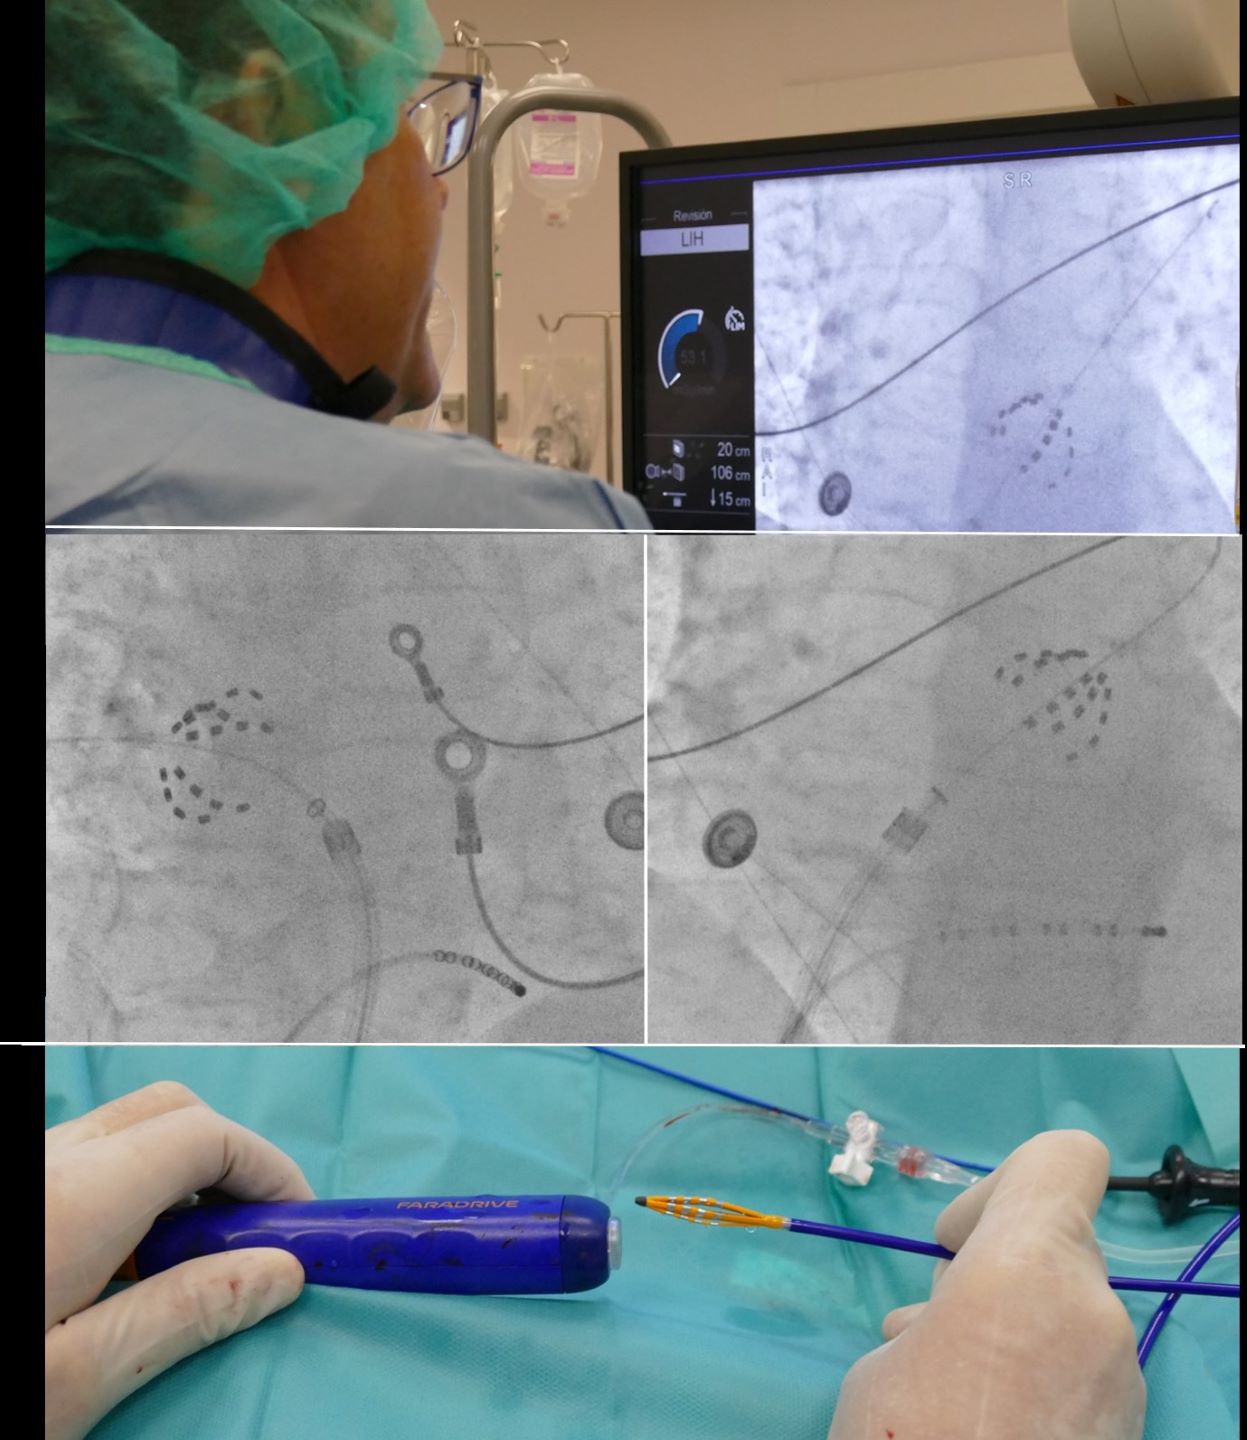

30 de abril de 2024La Unidad de Arritmias del Hospital Universitario Ruber Juan Bravo incorpora el sistema Farapulse para el tratamiento de la fibrilación auricular• Se trata del sistema más novedoso en todo el mundo para el tratamiento de la fibrilación auricular, cuya principal ventaja es la seguridad y la red...

3 de octubre de 2024La ablación de venas pulmonares por electroporación permite corregir la fibrilación auricular respetando el resto de tejidosSe trata del sistema más novedoso en todo el mundo para el tratamiento de la fibrilación auricular, cuya principal ventaja es la seguridad y la reduc...25 de septiembre de 2024La edad, la apatía, la ansiedad, nivel educativo y antecedentes familiares, factores a tener en cuenta para predecir la progresión del deterioro cognitivo